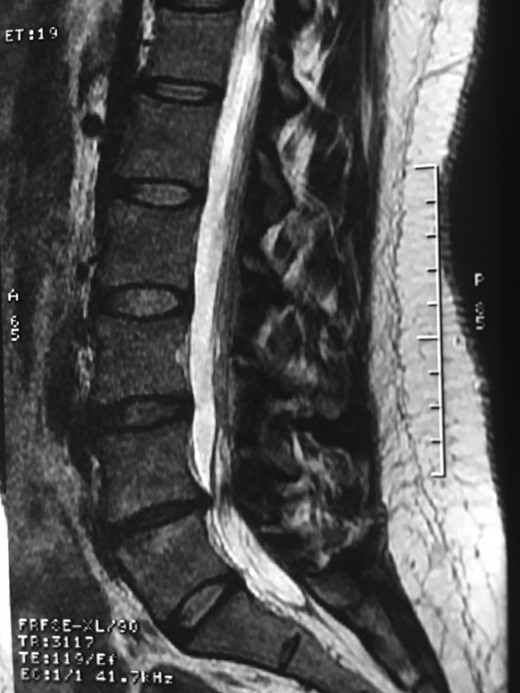

A 42-year-old female presented to the clinic with a history of chronic low back pain. She reported no relevant medical history. She had already been treated in the last 4 years by general practitioners with analgesics and home based physiotherapy with no satisfactory results. She had two previous admissions to the emergency department where morphine was prescribed to control the pain on her lower back. She was under ambulatory treatment with diclofenac, and tizanidine with partial relief of symptoms. Her main complaint was pain on the lower lumbar back with no radiation to the lower extremities. In her physical evaluation she presented limitation to full rotation and bending of the lumbar spine due to pain. Lasegue sign was negative, sensitivity, reflexes, sagittal balance, distal muscular strength and pulses were normal. Radiographs showed an overdeveloped left transverse process of the fifth lumbar vertebra which contacts with the sacrum at the left sacral wing with signs of degeneration at the same site (Fig. 1). Magnetic resonance imaging (MRI) studies were obtained (Figs 2–5). The patient was taken to the operating room where infiltration with 1 mL of lidocaine and 40 mg of Triamcinolone was performed in the pseudoarticulation between the left transverse process and the sacrum under fluoroscopic guidance. She reported a complete relief of pain after the procedure. At three months follow-up she was managed with strengthening and stabilizing exercises for the lumbar spine and postural education was initiated. She remains asymptomatic at her 12 months follow up.

Showing the protective effect of the limitation of the motion in the distal disc to the anomaly.

The partial fusion at the lower part of the lumbosacral transition produces important alterations in normal biomechanics at the levels immediately above and below the LSTV. Changes such as hypermobility and abnormal torque moments are present at the level above the LSTV, predisposing it to early degeneration (early disc pathology and facet joint degenerative disease). Restricted movement below the LSTV produces a protective effect against degeneration of disc and facets and is related to changes (facets are smaller and coronally oriented) in the dimensions of the lower level facet joints [7]. These alterations can be verified in the adjacent levels of the LSTV in our patient.